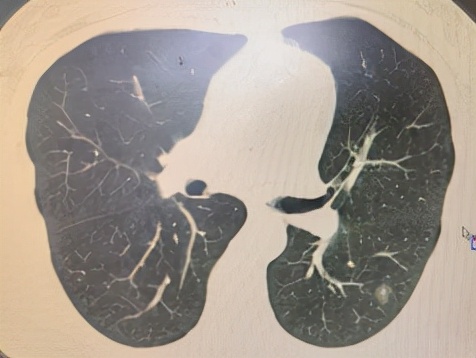

低剂量CT检查:肺结节影

(1) 对于肺癌高危人群,建议行低剂量螺旋CT (LDCT)筛查。

(2) 若检出肺内结节,做肺癌自身7项抗体”检测。(肺癌防治指南推荐方法之一)

(3) 携带CT及肺癌七抗检测结果肺结节门诊就诊,随访,及早发现肺癌,及早治疗。